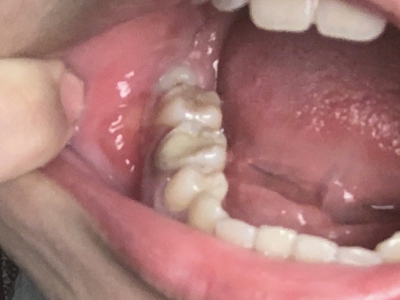

阻生牙是指由于邻牙、骨或软组织的阻碍而只能部分萌出或完全不能萌出,且以后也不能萌出的牙。引起牙阻生的成因,主要是由于颌骨缺乏足够的空间容纳全部恒牙。常见的阻生牙为下颌第三磨牙、上颌第三磨牙及上颌尖牙。

阻生牙可反复引起冠周炎,或引起邻牙牙根吸收和破坏,位置不正,不能完全萌出,好发部位是上、下颌第三磨牙。